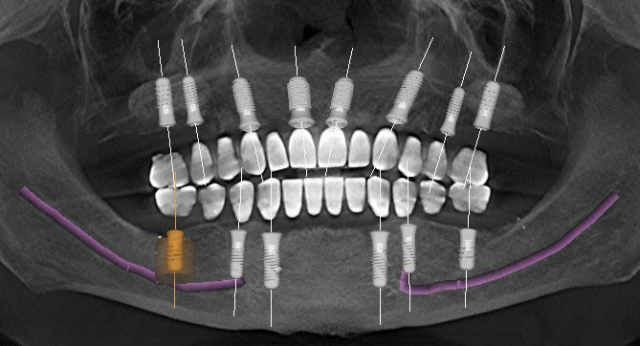

While six dental implants would work for segmented crown and bridge restorations, eight dental implants in the edentulous maxilla would allow progressively longer fixed bridge segments while moving more anterior in the arch. Having dental implants in the #3, #4, #6, #7, #10, #11, #13, and #14 areas provides for single units in the maxillary molar areas with a four-unit fixed bridge in the anterior segment, where we would typically notice significantly less functional chewing forces. The segments allow the opportunity to limit the repair cost should a restoration chip or fracture occur.

There are anatomical limitations that may alter our preferred treatment plan. The general anatomy of the edentulous maxilla is shaped like a dome, with the platform of the dental implant oriented toward the facial/buccal aspect, while the apical aspect is more medial/palatally positioned.

The more implants planned, the more likely the apex of the adjacent dental implants to come too close or to touch … more likely for implants planned in the premolar — canine — lateral area. Another more common anatomical limitation for dental implant placement and position relates to the maxillary sinus’s position, height, and width.